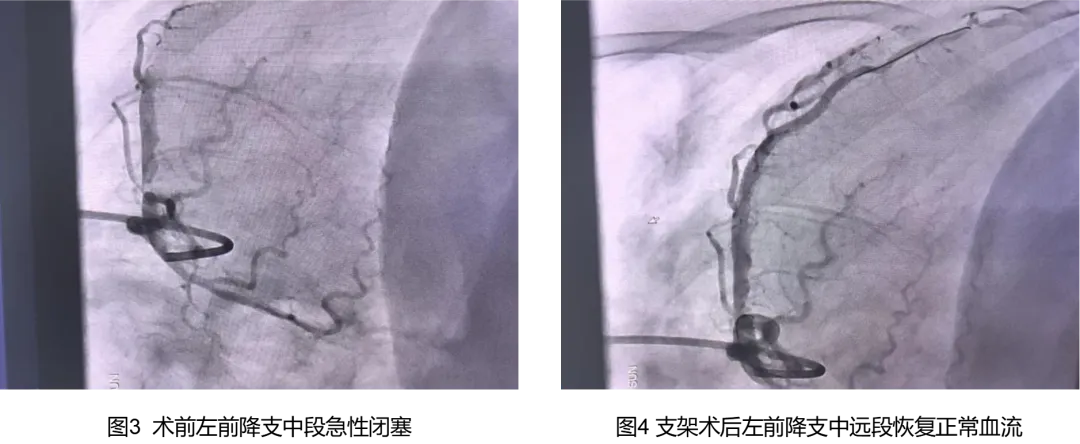

3.90分钟开通血管:抢救成功后,介入团队火速进行心脏支架手术,90分钟内打通闭塞血管,恢复血流。

终极武器:心脏支架手术力挽狂澜在稳定患者心律后,心血管介入团队发现其左前降支中段完全闭塞,血栓严重。通过球囊扩张、药物溶栓和支架植入,血流终于恢复畅通。“这类患者每一秒都是生死较量,既要抢时间开通血管,又要严防二次室颤。”援疆专家沈白医生强调。